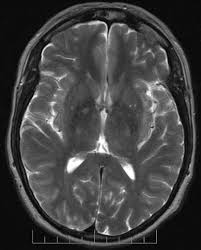

Brain Imaging

Brain imaging is necessary to detect the presence of hypothalamus function disorders. So, your doctor can perform the diagnostic to get a clear picture. To get clearer results, your doctor administers hormonal injections. It is followed by imaging tests like brain imaging or MRI.